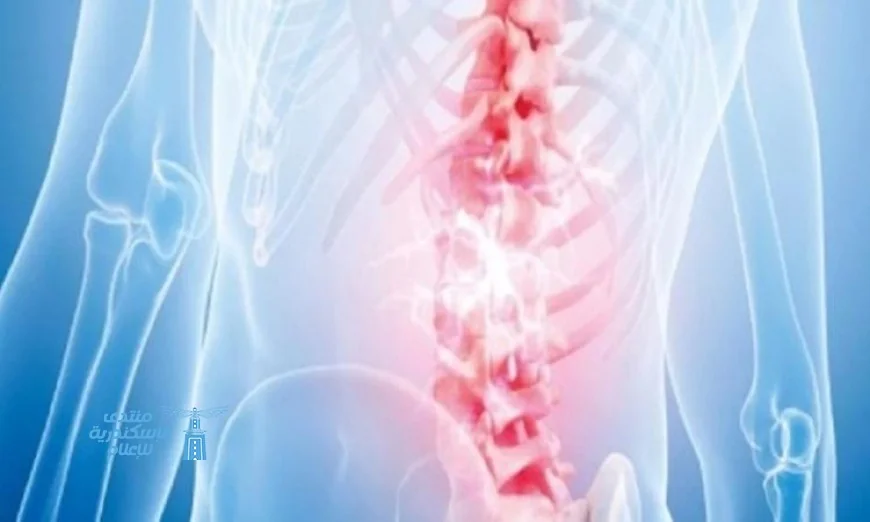

اكتشف طريقة مبتكرة للتخلص من آلام أسفل الظهر المزمنة

اكتشاف علاج جديد لآلام أسفل الظهر المزمنة

توصل الباحثون إلى طريقة مبتكرة وغير تقليدية لعلاج آلام أسفل الظهر المزمنة من خلال استخدام هرمون طبيعي يُعرف باسم “هرمون جار الدرقية”. أظهرت الدراسات أن لهذا الهرمون دوراً في تقوية العظام، بالإضافة إلى قدرته على تقليل الإحساس بالألم بشكل مباشر.

آلية عمل الهرمون

وضحت الدراسة أن “هرمون جار الدرقية” يساهم في منع نمو النهايات العصبية الحساسة داخل الأنسجة المتضررة في العمود الفقري. عند حدوث إصابة، يعمل الهرمون على تشكيل “حاجز وقائي” يمنع الأعصاب المسؤولة عن الألم من دخول المناطق المصابة.

يؤدي هذا التأثير إلى تقليل الإشارات العصبية التي تنقل الألم إلى الدماغ، مما يساهم في تخفيف الشعور بالألم من مصدره بدلاً من مجرد إخفاء الأعراض.

نتائج التجارب

جرى اختبار هذا الهرمون على بعض الحيوانات، حيث أظهرت النتائج أن حقنه أدى إلى تعزيز قوة الأنسجة في العمود الفقري مع حدوث انخفاض ملحوظ في حساسية الألم لدى الحالات التي تم تجربتها.

مقارنة مع العلاجات التقليدية

تعتمد معظم العلاجات الحالية لآلام الظهر على تسكين الأعراض فقط باستخدام المسكنات، دون معالجة السبب الجذري للألم. في المقابل، يستهدف هذا الاكتشاف الجديد السبب البيولوجي المباشر للألم، مما يجعله نهجاً مختلفاً وأكثر تطورًا في مجال العلاج.

إمكانات مستقبلية

يشير الباحثون إلى أن هذا الاكتشاف قد يفتح الأبواب لتطوير أدوية مسكنة حديثة وموجهة، تسهم في تقليل الألم دون الحاجة إلى استخدام مسكنات قوية قد تسبب آثاراً جانبية.